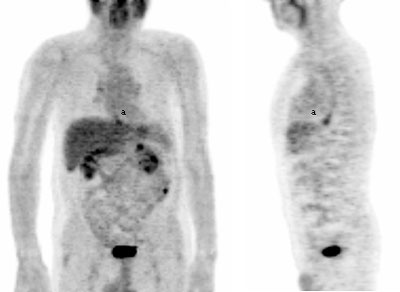

Fig. 2. - Imágenes coronal y lateral de tomografía por emisión de positrones de cuerpo completo. Mujer de 18 años en estudio por lesión naso-sinusal, donde se observa aumento del metabolismo de la [18]FDG en cerebro, área de musculatura oculomotora (a), musculatura cervical, paraclavicular y paravertebral. Asimismo se aprecia aumento del metabolismo de la [18]FDG en ventrículo izquierdo.. Volver